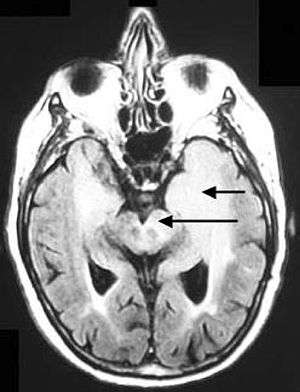

The pulse sequence is an inversion recovery technique that nulls fluids. For example, it can be used in brain imaging to suppress cerebrospinal fluid (CSF) effects on the image, so as to bring out the periventricular hyperintense lesions, such as multiple sclerosis (MS) plaques.[1]

- Lacunar infarction